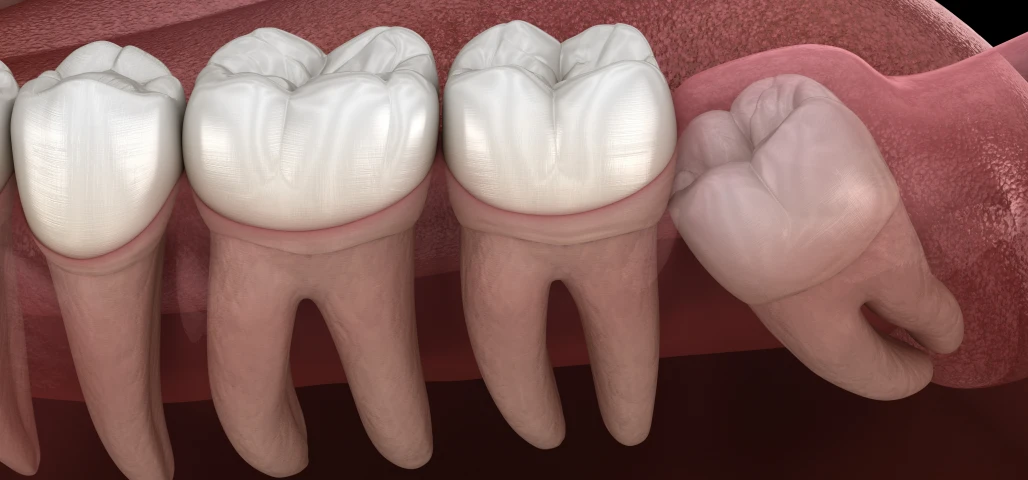

La chirurgie orale regroupe un ensemble d’interventions réalisées au niveau de la bouche, des dents et des mâchoires, allant de l’extraction des dents de sagesse aux actes plus complexes comme les kystes, les freinectomies ou les préparations implantaires.